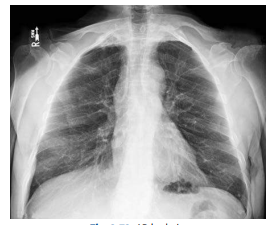

What chest projection is this?

PA Chest